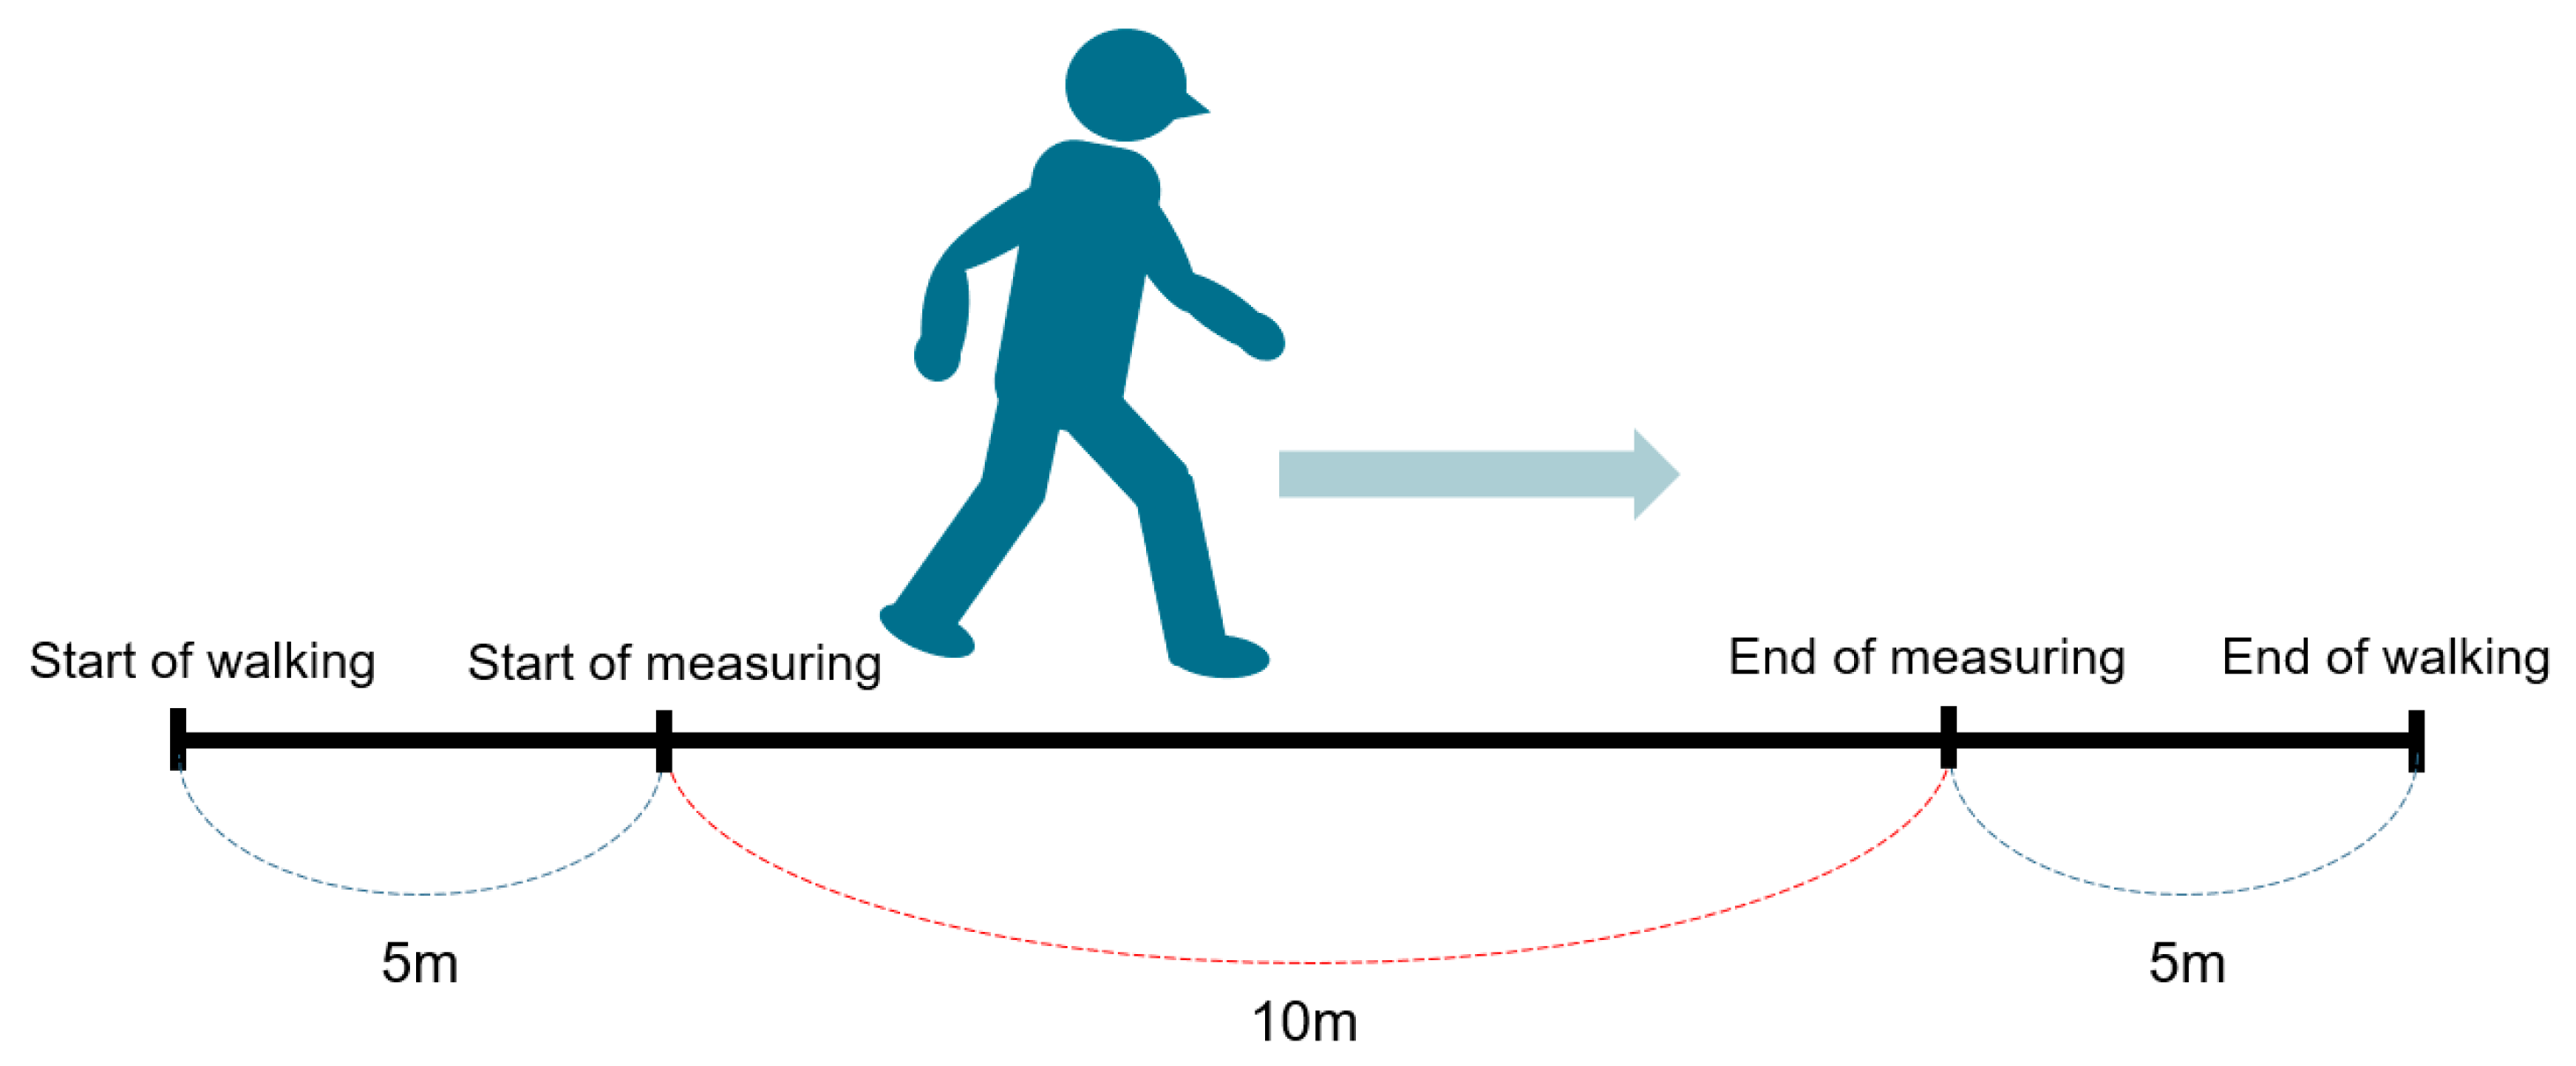

2.2. Outcome Assessment

2.2.1. Ten Meter Walk Velocity